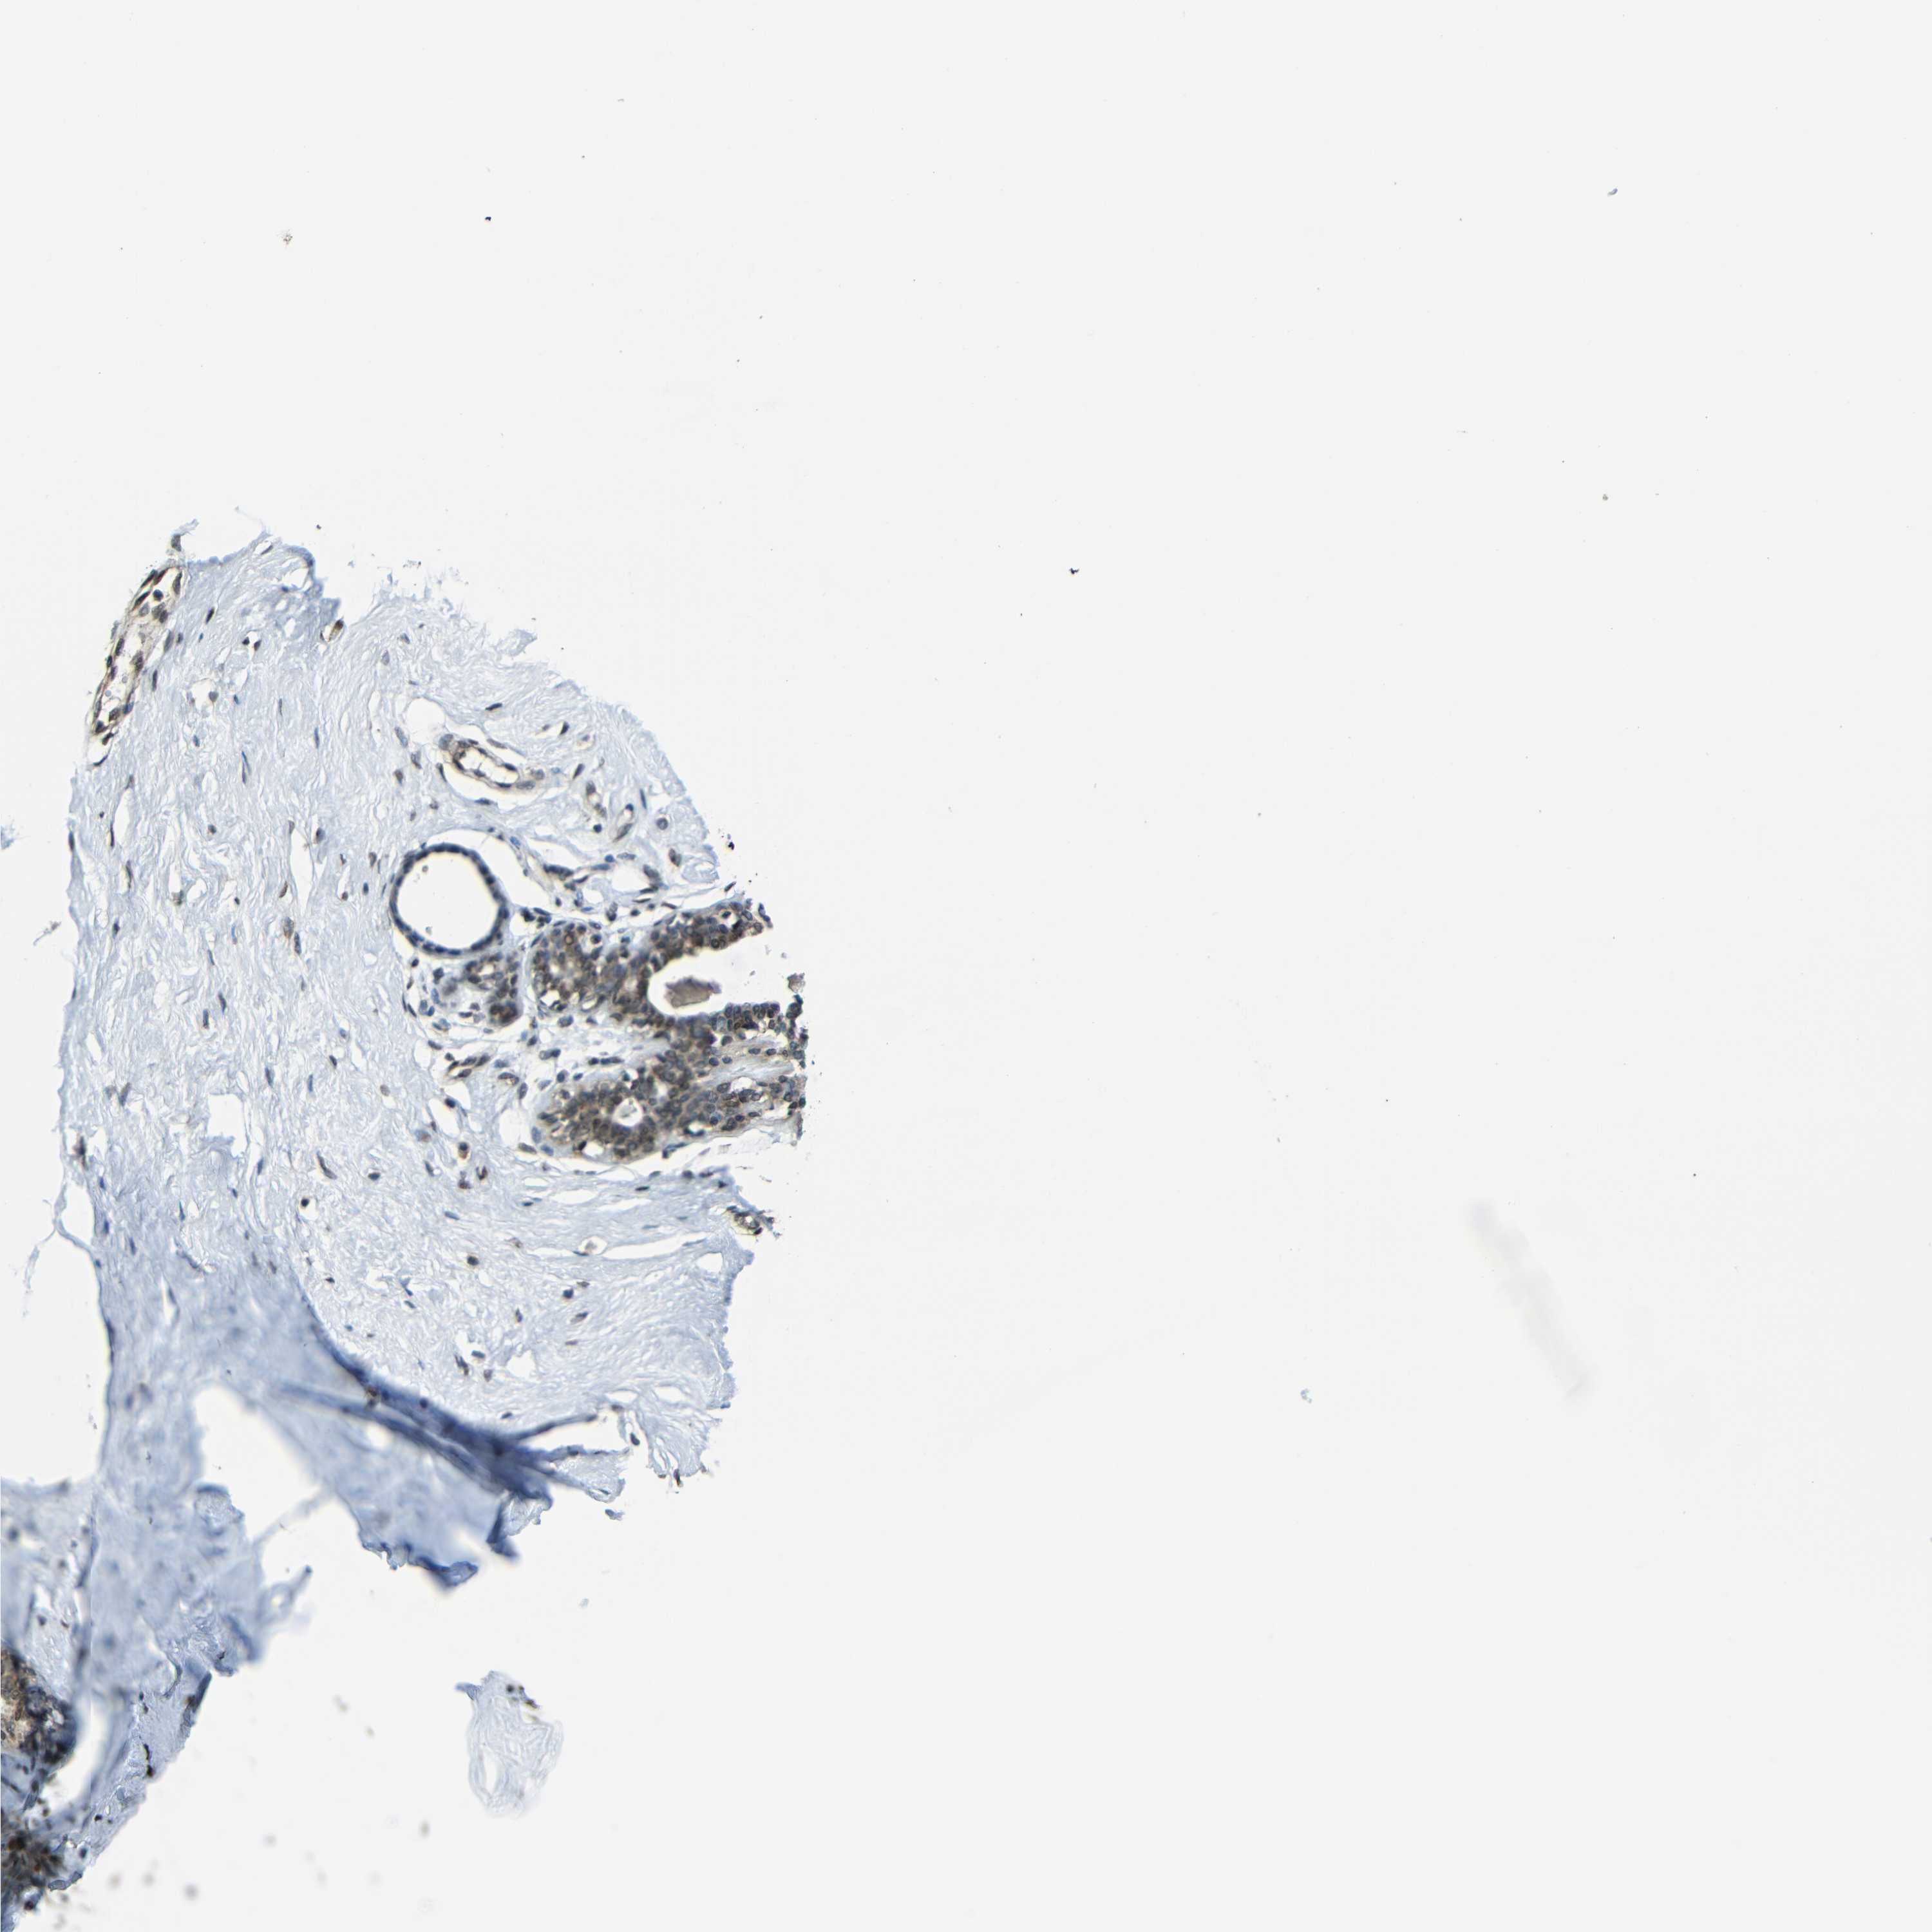

BREAST - Antibody stainingi

Antibody staining in the annotated cell types in the current human tissue is reported as not detected, low, medium, or high, based on conventional immunohistochemistry profiling in selected tissues. This score is based on the combination of the staining intensity and fraction of stained cells.

Each image is clickable and will lead to virtual microscopy that enables deeper exploration of all samples and also displays staining intensity scores, fraction scores and subcellular localization as well as patient and tissue information for each sample.

Antibody HPA019697Antibody CAB013718

Adipocytes HighNot detected

Glandular cells HighLow

Myoepithelial cells MediumLow